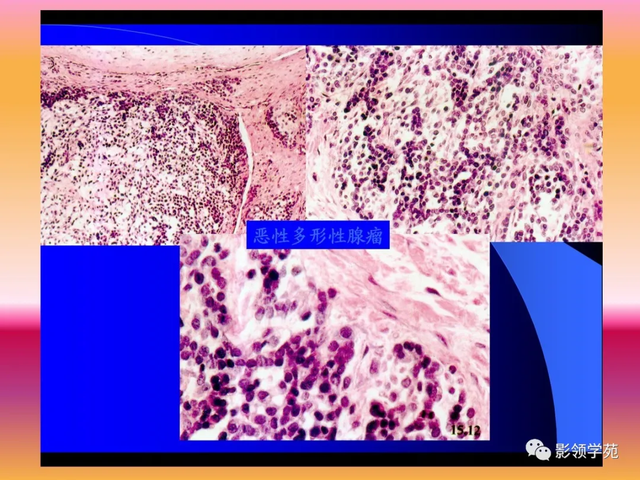

多形性腺瘤(混淆瘤)

多形性腺癌(pleomrphicadenom)是一种包膜情形 纷歧,光镜下以结构多形性而不是细胞多形性为特征的肿瘤。通常上皮和变异肌上皮因素 与黏液、黏液样组织或软骨样组织混淆存在。曾以为 黏液软骨样组织来自间叶组织,故又称为混淆瘤(mixedtumor)。

恶变:

恶性多形性腺瘤可以是:良性多形性腺瘤合并癌,最为常见;癌及肉瘤并存;良性多形性腺瘤有远处转移。良性多形性腺瘤存在的时间越长,恶变率高,若是 不实时切除,约25%汇合并癌,对于发病年岁 较大者,病程较长而近期肿物有显着 增大者,病灶界线 不清并伴有大片坏死的,均应高度嫌疑 有恶性改变。

病理:

肉眼视察,多呈不规则结节状。剖面多为实性,灰白色或黄色,有白色条纹,可见囊腔形成,囊腔内含透明黏液,有时可见可见浅蓝色的软骨样组织或黄色的角化物,偶见出血及钙化。肿瘤周围有厚薄纷歧的包膜,多数肿瘤包膜完整,可是 以黏液样结构为主的肿瘤或发生于小涎腺者包膜可不完整或无包膜。复发肿瘤多因由 于手术历程中的莳植 ,常为多灶性。